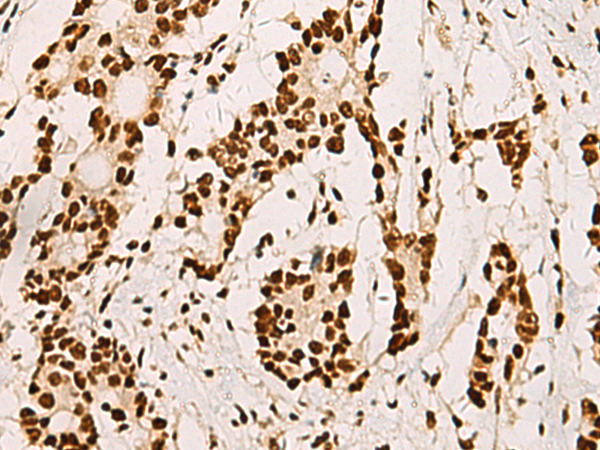

ELISA, IHC |

IHC positive control: |

Human colorectal cancer and Human cervical cancer |

IHC Recommend dilution: |

50-200 |